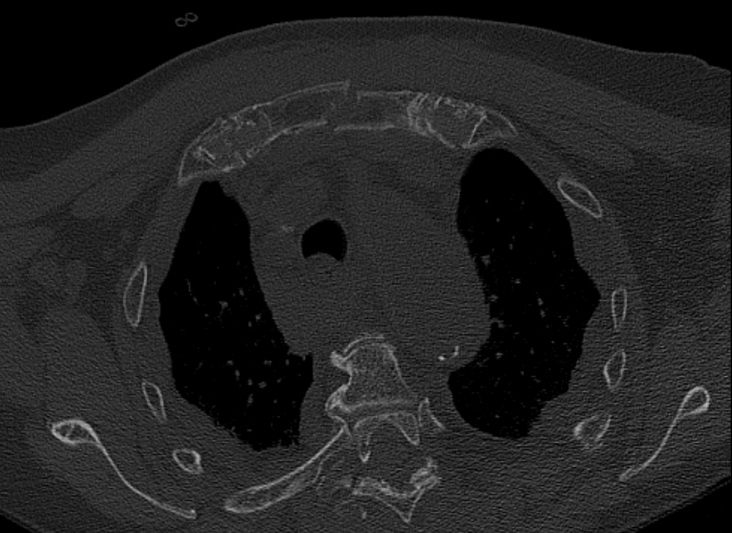

Fall from 4-meter height

Mechanism of injury: An 81 year old woman fell onto her back from a height of 4 meters. (Fig 6a-d) She sustained a multiple sternal fracture concomitant with a fracture of the 5th thoracic vertebra resulting in an unstable injury of the trunk. Fortunately she did not show any neurologic deficit or paraplegia.

Diagnosis: Complex sternal fracture with multidirectional instability (longitudinal fracture of the manubrium, transverse fracture involving 3 levels of manubrium and corpus sterni) Concomitant to this was a fracture of the 5th thoracic vertebra (AOB2.1).

Treatment: The sternal fracture has been managed by open-reduction and internal fixation with a locked plate osteosynthesis (MatrixRIB, I-Plate) through an anterior approach in the mid-line. b The thoracic spine has been managed employing dorsal instrumentation (internal fixator th4-th6).

Post-operative outcome: The wounds and bone healed uneventfully. Breathing was possible spontaneously without any restrictions. The patient reported on a significant reduction of the pain immediately after the operative procedure. Mobilization on the ward started on the first day after the procedure. No complications such as secondary failure, non-unions, pain or deformity of the chest wall could be seen during the follow up examinations of 6 and 12 weeks and 6 and 12 months.